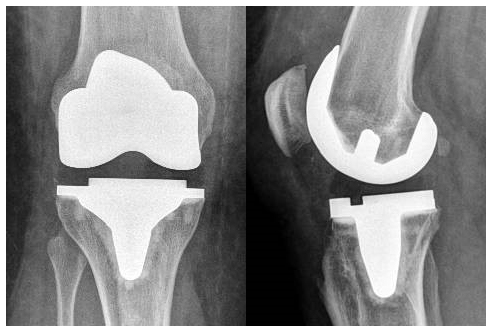

Because the knee joint consists of three different parts, a knee prosthesis usually also has three separate parts: an upper leg component, a lower leg component, and a kneecap component(figure 1). In principle, there is no age limit and both younger and older patients are eligible. Modern prostheses last an average of fifteen to twenty years. After that period, if the prosthesis shows wear or begins to loosen, it can be replaced. It used to be said that only 1 replacement was possible. With today’s techniques, multiple replacements are possible. You may expect that a large part – if not all – of your osteoarthritis pain has disappeared, or has become much less. The mobility of the joint remains about the same as before the operation. How flexible the knee becomes after surgery is strongly determined by how much and how well you exercise afterwards. As soon as you have healed after placing your prosthesis, you can walk again, cycle and swim. If your rehabilitation goes well, you may do sports to a limited extent, such as playing tennis and golf.

The full or total knee arthroplasty is the most frequently performed knee arthroplasty. This is used when the entire knee is worn out. During the procedure, the damaged cartilage is removed and replaced with a new metal covering about 9 mm thick. This knee prosthesis is attached to the femur and tibia with a kind of bone glue or cement. Between the 2 metal components is a plastic component made of very hard and wear-resistant polyethylene over which the knee can flex and stretch smoothly.